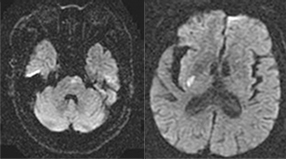

뇌경색 초기증상에 대하므로 살펴볼게요니다. 뇌에도 혈관이 있어서 피가 흐르고 있어요. 뇌에 있는 혈관이 막혀서 뇌의 일부가 손상되는 것을 뇌경색이라고 말해요. 뇌혈관이 막혀 뇌가 손상되면 장애가 발생할수 도 있으므로 뇌 연관 질환은 각별한 주의가 필요해요.

뇌에 제공되는 혈액량이 줄어들게면 뇌가 수습해야 되는 역할들을 제대로 실행해 낼 수 없게 돼요. 뇌혈류가 연속적으로 감소되면 뇌조직에 괴사가 시작되고 괴사된 뇌조직이 회복 불가능한 상태가 되면 뇌경색이라고 진단을합니다. 그러므로 뇌경색 초기증상을 알아두고 방지해억제해하시는게 중요해요.

뇌경색의 주된 이유가 되는 것은 혈전이지요. 혈전이란 혈관 속에 피가 굳어진 덩어리를 얘기하는데 이것이 혈관을 막는 것이 뇌경색에 큰 영향을 줄 수 있습니다. 평균적으로 많이 발생하는 연령대는 5~60대이지요. 뇌경색은 양쪽 뇌에 모두 나타나는는 것이 아니라 주로 한쪽 뇌에만 발생하지만, 주로 한쪽 팔다리가 마비되었다거나 얼굴 근육이 굳어버리기도 해요. 그렇기에 뇌경색 초기증상이 발생한다면 민첩하게 대응를 해야 하겠습니다.

또 뇌경색의 까닭은 혈관의 협착을 유발시키는 동맥경화증이고요. 동양에서는 뇌내동맥경화증이, 서양에서는 경동맥동맥경화증이 많이 나타나고다. 그리고 흡연, 고지혈증, 당뇨병, 고혈압, 건강에 옳지 않은 식습관, 스트레스 등도 뇌경색을 발생시키는 위험요인입니다.모든 질병에 단일 이유가 되는 것이 없듯이 뇌경색도 단일 이유가 되는 것이 아닐 수 있고요.